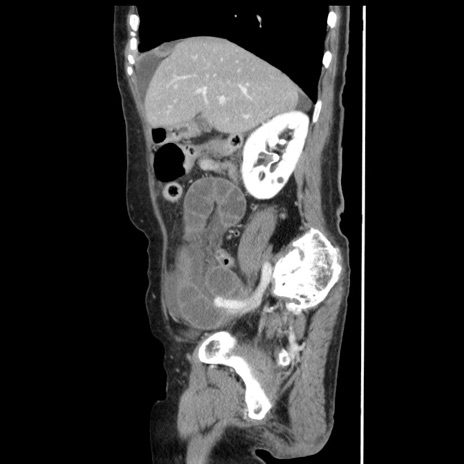

横断像

【症例】80歳代女性

【主訴】腹痛

【現病歴】8時間前から腹痛あり来院。

【既往歴】糖尿病、脂質異常症、子宮体癌にて子宮全摘術

【身体所見】意識清明・会話良好だが腹痛で苦悶様、全腹部にわたって反跳痛と圧痛あり

【データ】WBC 13600、CRP 0.14、LDH 224、CK 90